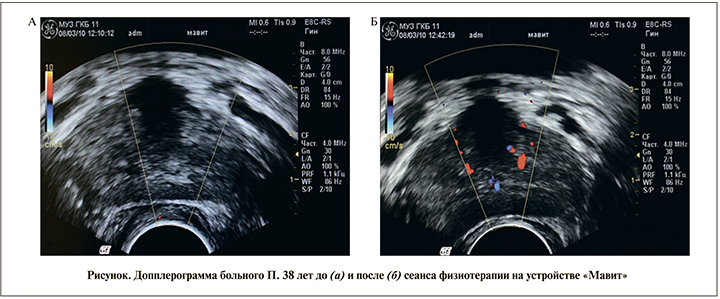

Для оценки биотканевого влияния устройства «Мавит» на кровообращение предстательной железы и окружающие ткани 10 больным группы ХП до и после физиотерапевтического сеанса проведено трансректальное УЗИ простаты в режиме цветного допплеровского картирования. Определили пиковую скорость кровотока, индекс периферического сосудистого сопротивления, а также плотность органного сосудистого рисунка.

Для оценки состояния кровотока в предстательной железе после сеанса локальной физиотерапии на устройстве «Мавит» 10 больным группы ХП проведено трансректальное УЗИ простаты в режиме цветного допплеровского картирования до и после лечебного сеанса. Во всех наблюдениях зарегистрировано улучшение микроциркуляции в ткани предстательной железы. Применение аппарата «Мавит» способствовало выраженному усилению кровообращения по всему сосудистому коллектору простаты (см. рисунок). Средний показатель линейных пиковых скоростей по сравнению с исходными данными увеличился в 1,1 раза, уменьшилась величина индекса резистентности в 1,2 раза. Средний показатель плотности сосудистого рисунка увеличился более чем в 2,5 раза.